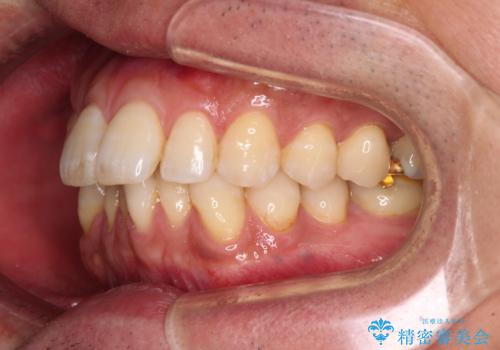

- 口元の突出感を気にして来院された患者様です。

強い咬合力と上顎前歯の傾斜により前歯が突出し、唇が閉じにくい状況であったため、上下左右の第一小臼歯4本を抜歯し、ワイヤー装置にて矯正治療を行うこととしました。

非常に咬合力が強いため、抜歯したスペースが閉じるのか不安でしたが、順調に歯が移動し、予定よりも早く治療を終えることができました。